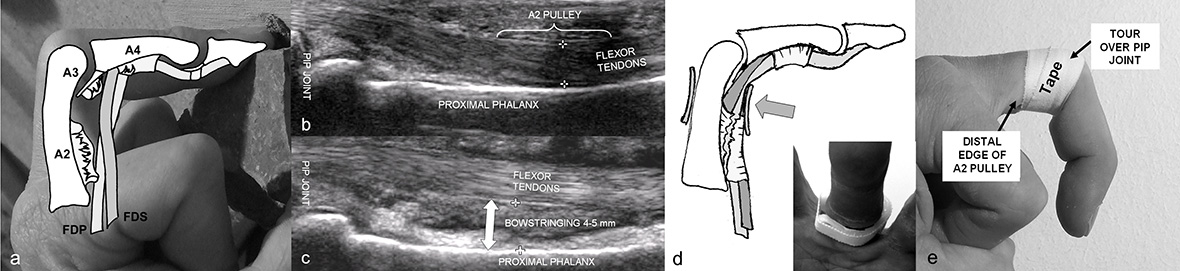

Figure 2

Finger flexor tendon sheath (A) with complete disruption of the A2 and the A3 pulley, partial disruption of the A4 pulley leading to bowstringing of the deep (FDP) and the superficial (FDS) flexor tendons. Ultrasound view of the normal anatomy (B) and of a disrupted A2 pulley (C) with an apparent bowstringing of the flexor tendons. A pulley protection ring (D) brings the flexor tendon back to normal position. Properly applied pulley tape (E) prevents flexion of the PIP joint of more than 80°.

The diagnosis of a pulley disruption is based on the history (pop or snapping sound) and on clinical examination, where a painful flexor tendon bowstringing can be palpated during resisted finger-flexion. The lift-off or bowstringing of the tendon visualised by ultrasound [21, 22] or a magnetic resonance imaging (less accurate) confirms the diagnosis. The treatment recommendations are controversial as some hand surgeons still treat single pulley-disruptions with reconstruction [23]. However, most accept treating single pulley-disruption conservatively eversince Schöffl [24] showed that even with non-operative management no objective or subjective functional loss occurred. Non-operative treatment is generally functional. The healing-time is between 2 to 3 months and full load-bearing can be expected after 4–6 months.

We recommend the use of a special pulley protection ring (fig. 2) designed to protect the neuro-vascular bundles while allowing an adequate reposition of the tendon without compromising circulation within the finger. After two months, the ring is replaced by a pulley protection tape (fig. 2). To take strain off the healing pulley it is applied around the PIP-joint and inhibits flexion of that joint to more than 80° above which pulley load becomes particularly high [17, 19]. With this treatment regimen we were able to reduce the initial bowstringing at the A2-pulley to about 50% and at the A4-pulley to about 40%. If the injury is left untreated or protected only with a tape the amount of bowstringing remains the same. If, however, two or even more pulleys are disrupted (for instance A2 an A3 or A2, A3 and A4-pulley), the amount of bowstringing increases substantially leading to a loss to the active flexion range of motion of the finger and a reconstruction of the ligament has to be considered. This can be performed with a graft from the extensor retinaculum or a free tendon graft. The results of such interventions are generally good and do not differ much between techniques [13, 25, 26]. However, whether all these patients need a reconstruction at all is still being debated. We have seen a series of patients with multiple pulley ruptures who returned to their previous climbing level without restriction except for a small loss of flexion range of motion. It has to be taken into consideration that pulley reconstruction leads to a rehabilitation time of several months.